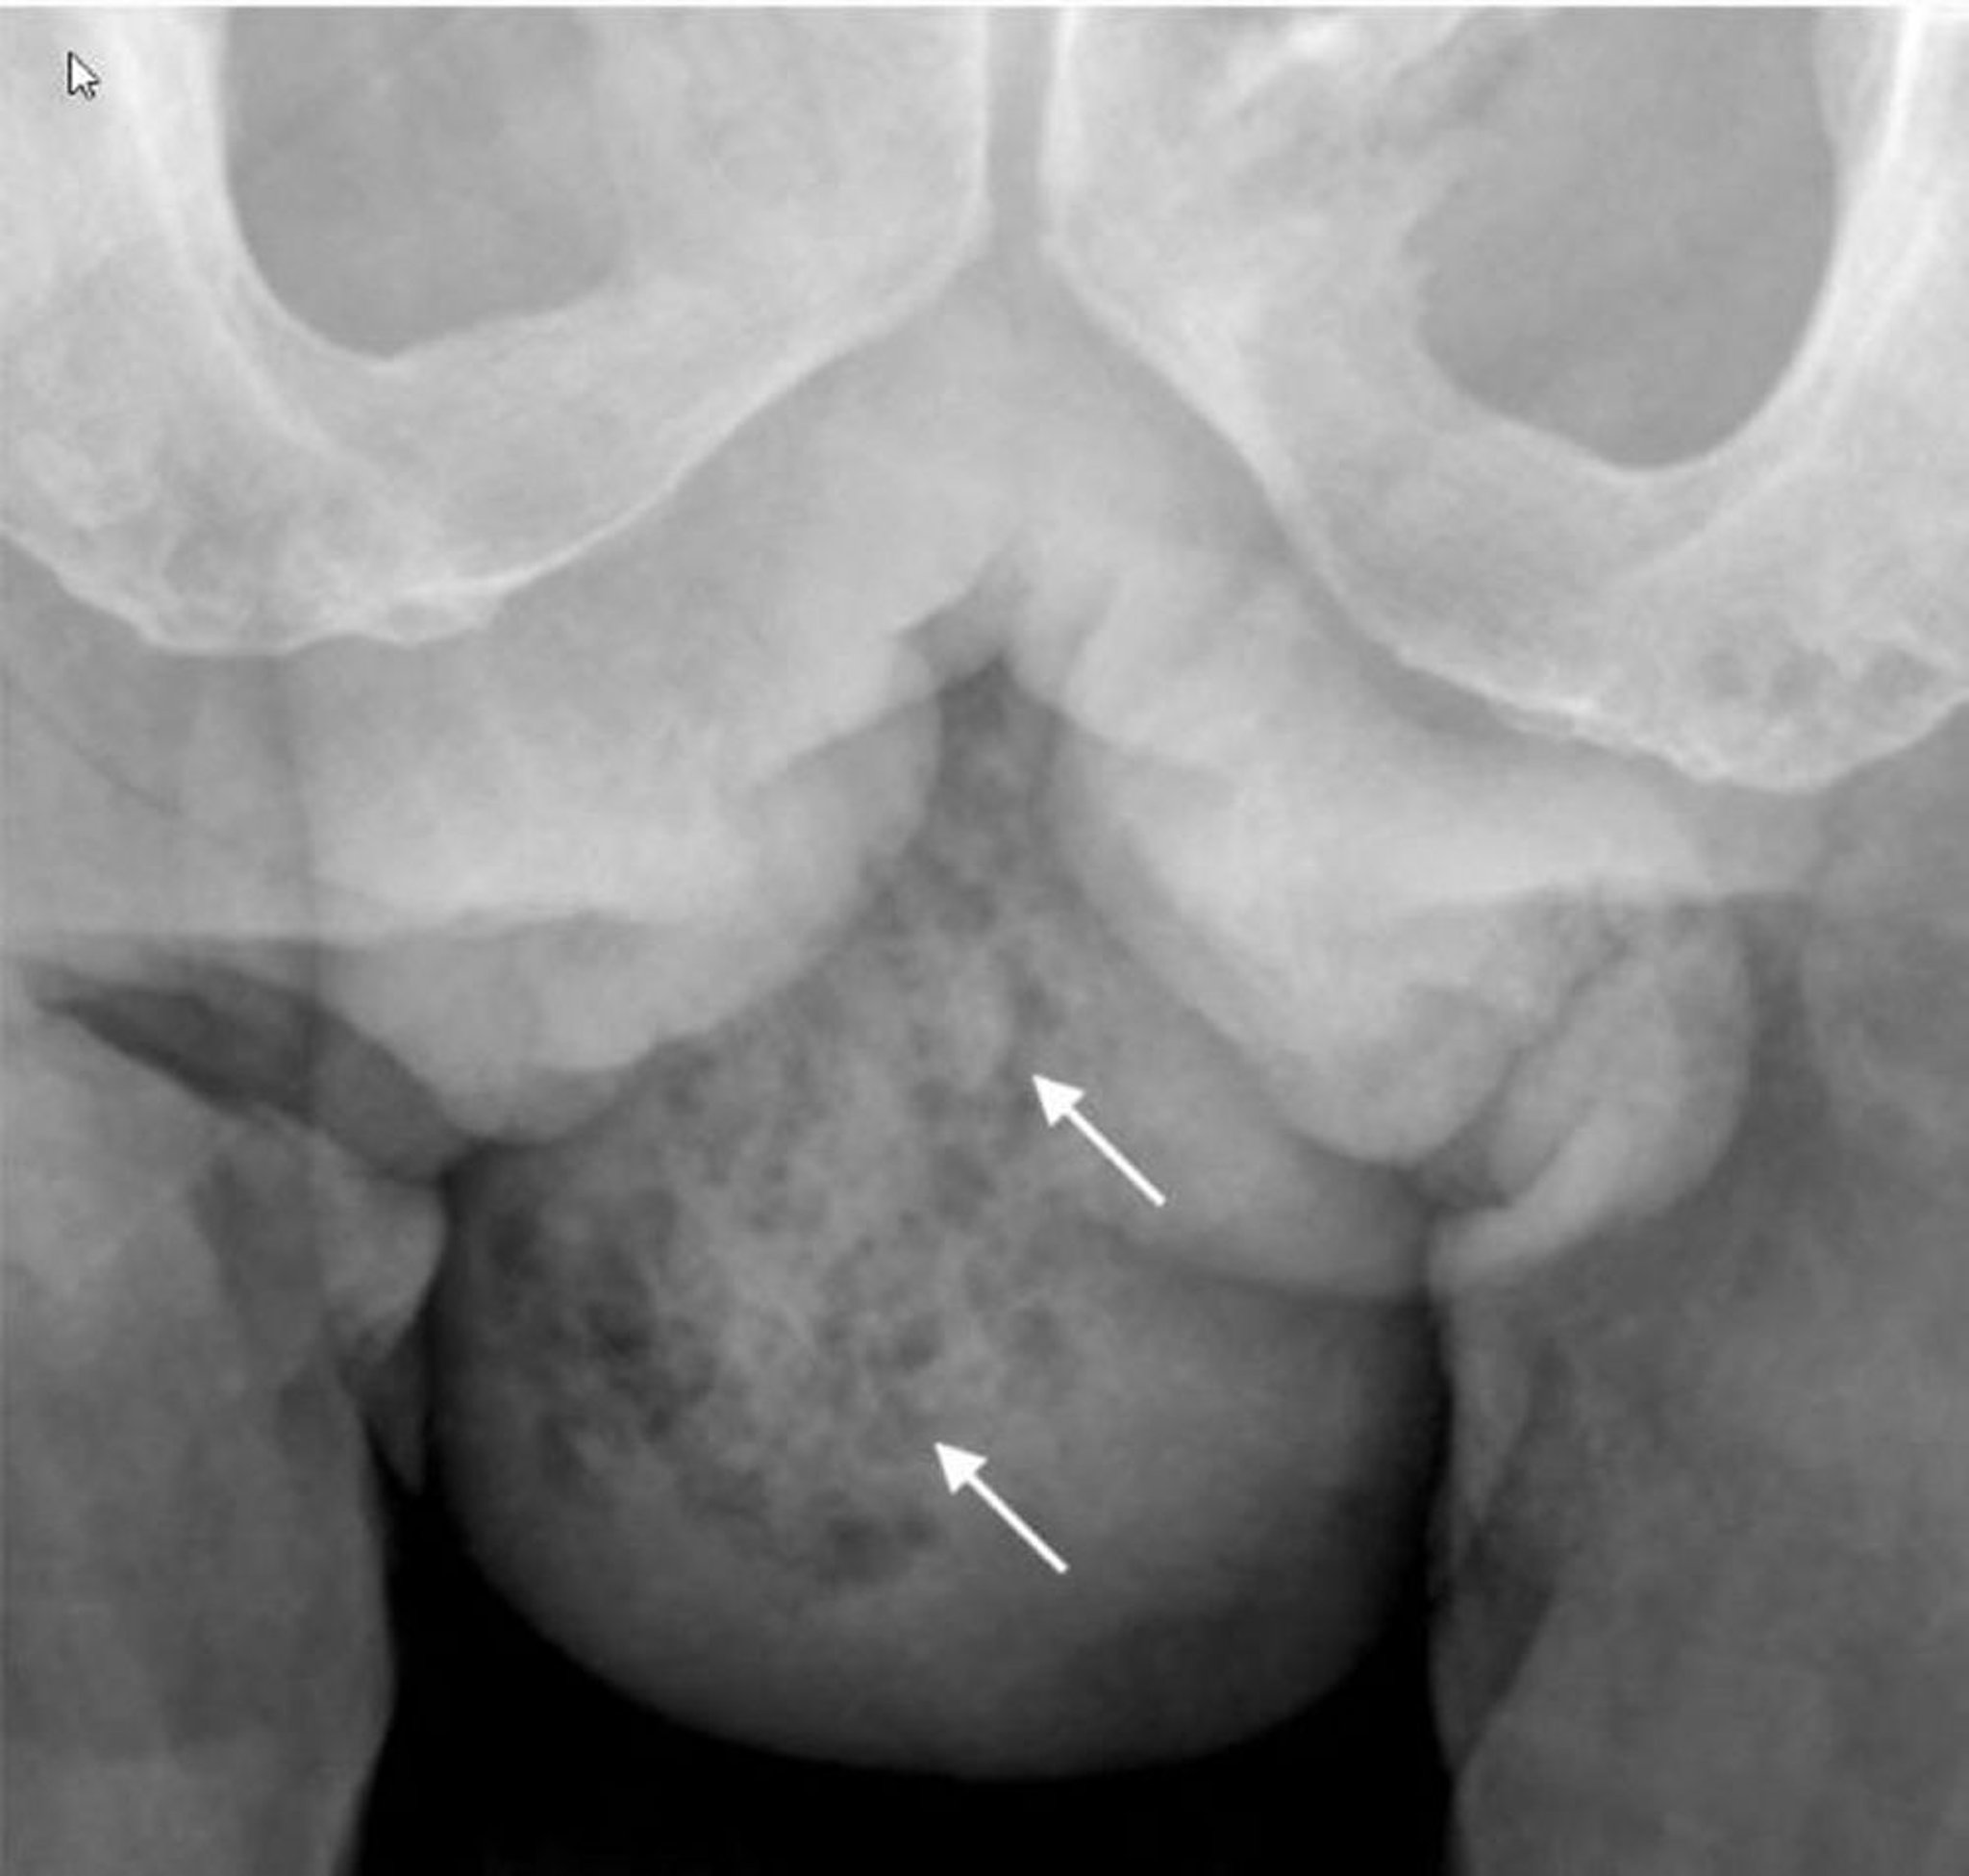

Гангрена Фурнье (рентген)

На данном рентгеновском снимке показан газ в мягких тканях в правой половине мошонки (стрелки).